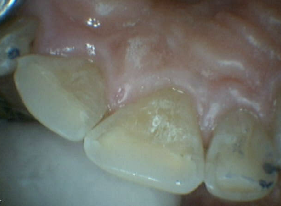

Worn Translucent Incisal Edges, Translucency Corrected with Hybrid Resins